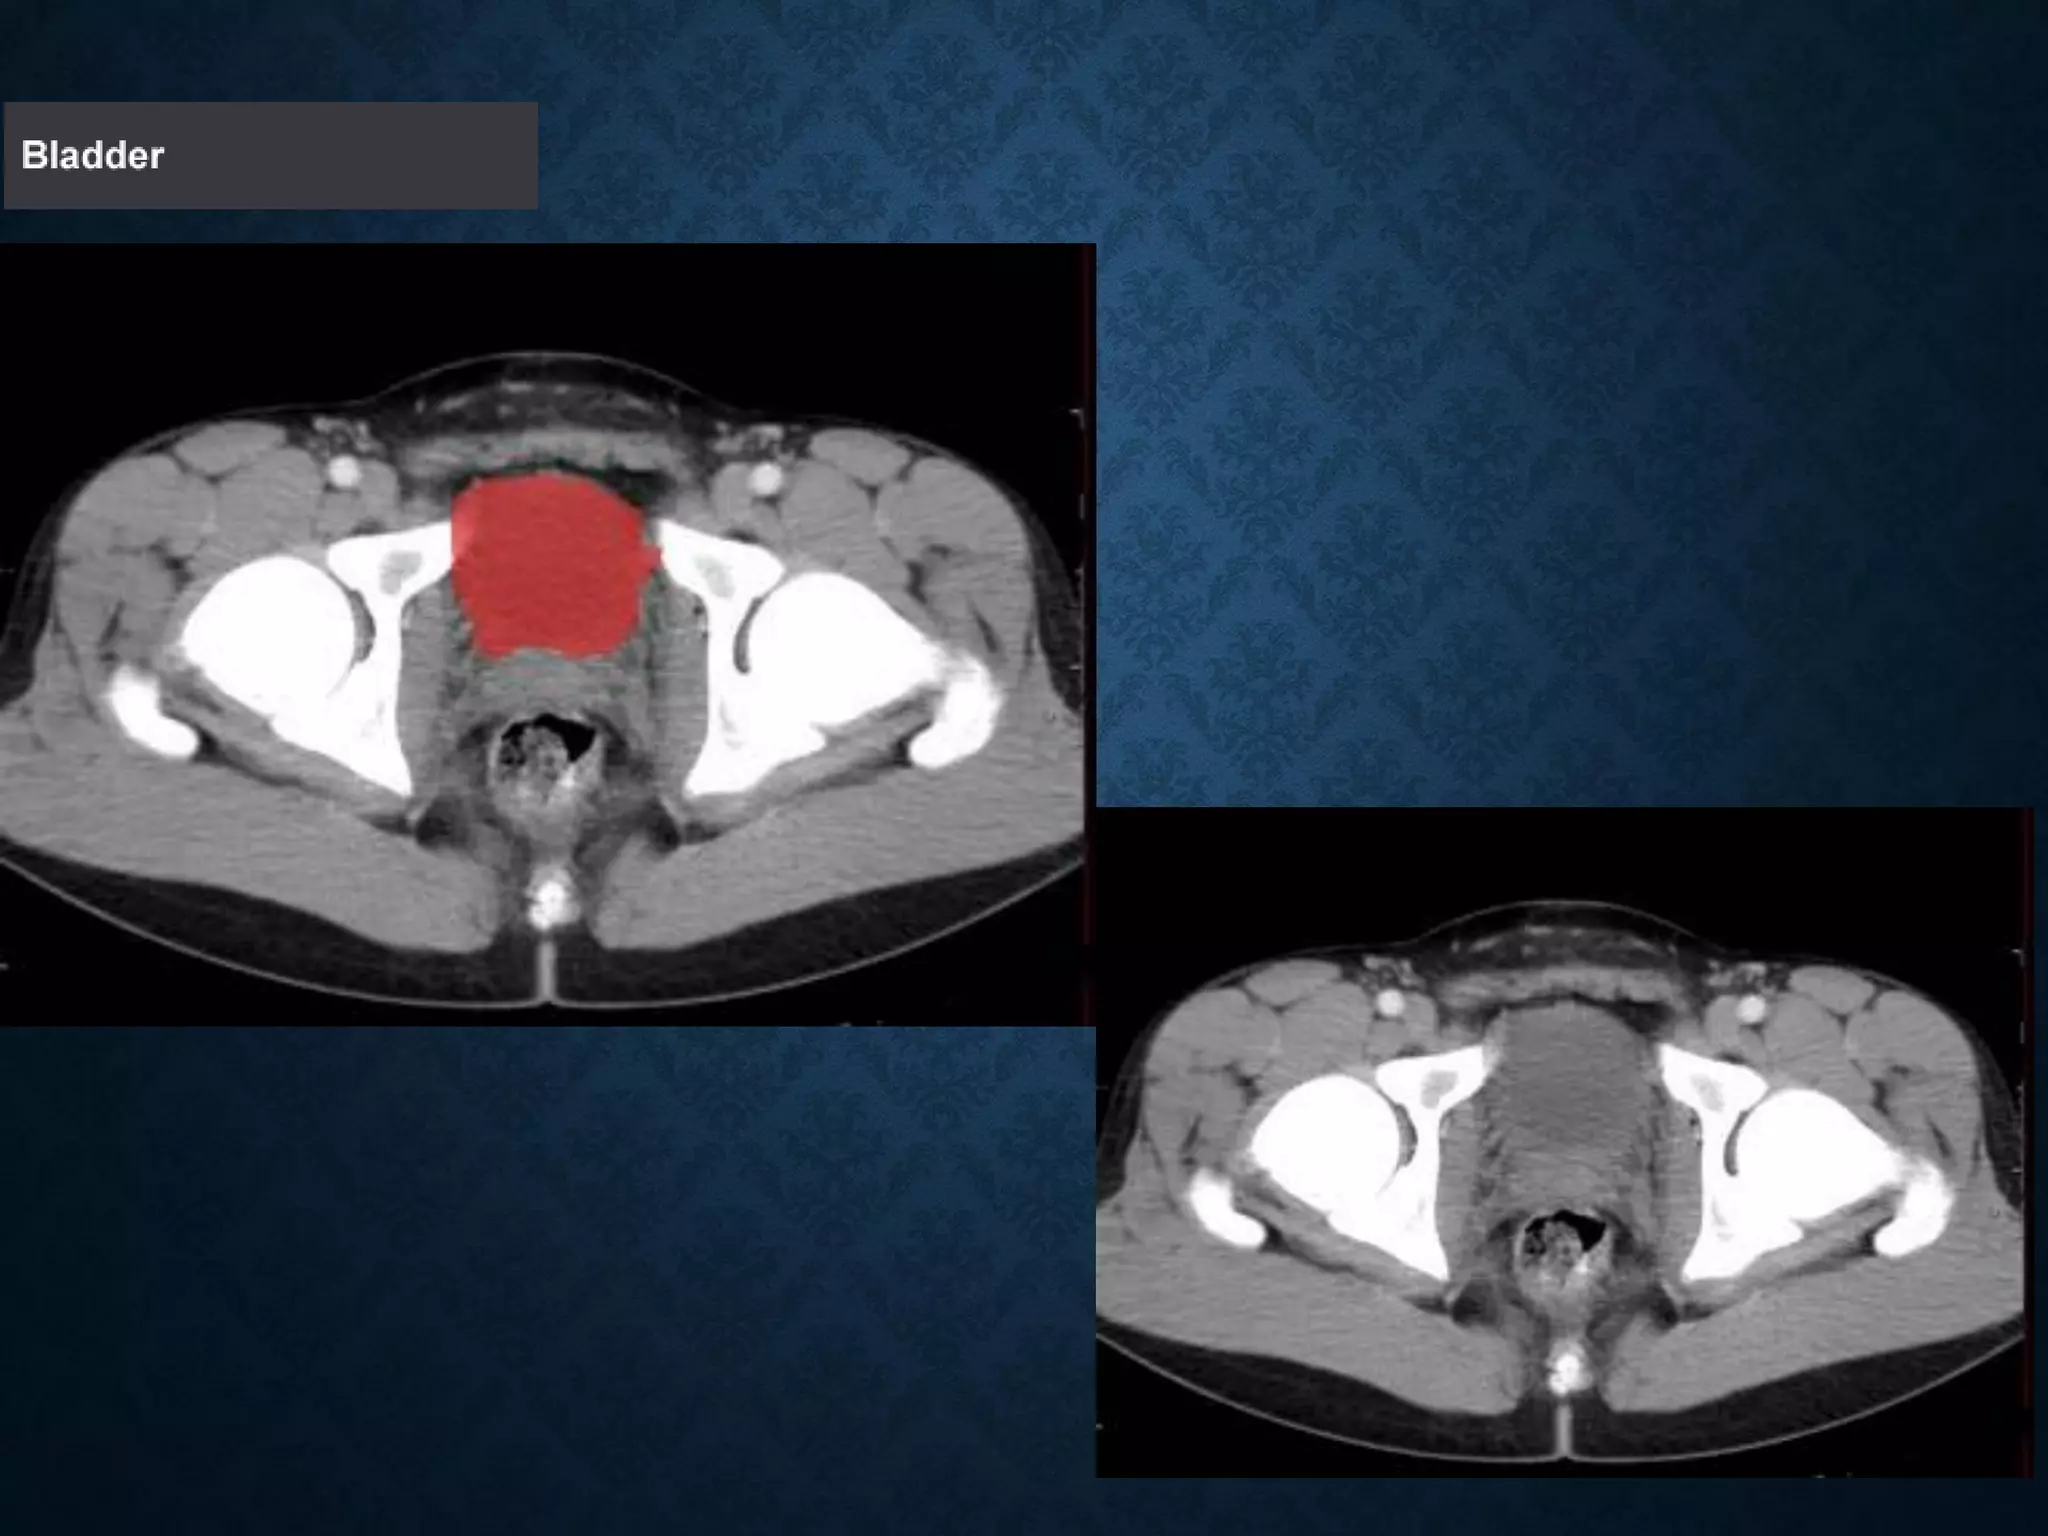

Identify the following structures in the body CT to the right. To view the location of the structure in the image click on

the label at the left and the structure will be indicated in the image. Abdominal CT scans typically begin just above

the diaphragm, so the first slice you see is of the lower chest.